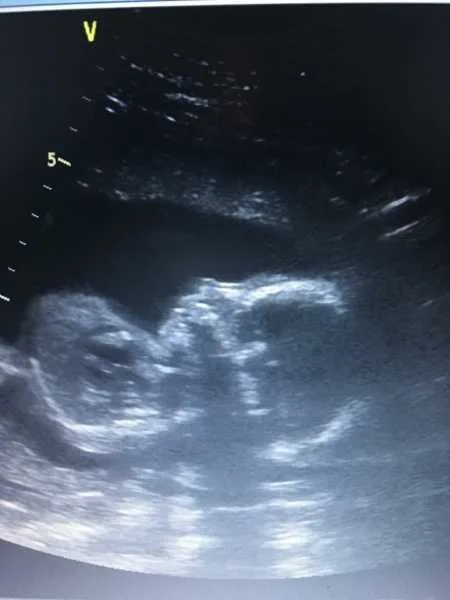

Through this dark season, they were introduced to hospice care and a nurse navigator named Jolenda. These caregivers and the staff at Choices Hospice became a lifeline. They arranged sonograms, explained the medical details, and gave the Mortons precious opportunities to bond with their baby boy. Their support reminded the couple that they were not alone even in pain. Nights were often filled with tears, but also with moments of faith. Brittany once read about heaven while soaking in the bath, and Josh described a vision of beauty and peace that convinced him their son would one day be safe in God’s arms.

As the due date approached, time seemed to slow. On March 5, 2017, Brittany noticed she hadn’t felt the baby move. At the hospital, doctors confirmed what they feared—baby Coehn had passed away in the womb. The couple endured 33 long hours of labor before meeting their son. On March 7, at 11:35 a.m., Coehn Ray Morton entered the world silently. The hospital room fell quiet, filled with sorrow. Yet when his parents held him, peace slowly washed over them.